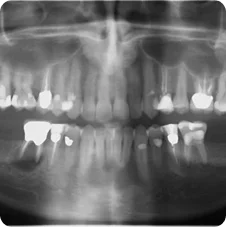

Pre-operative